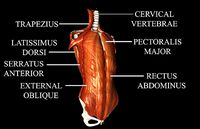

$40

Human Thorax Medically Accurate With Muscles

...curate with muscles

cg trader

thorax 3d model with all the muscles and bones, can be easily used for your 3d medical animations.

Chest Anatomy

...for muscular refence estudys. the chest, properly called the thorax is the superior part of the trunk located between...

cg_trader